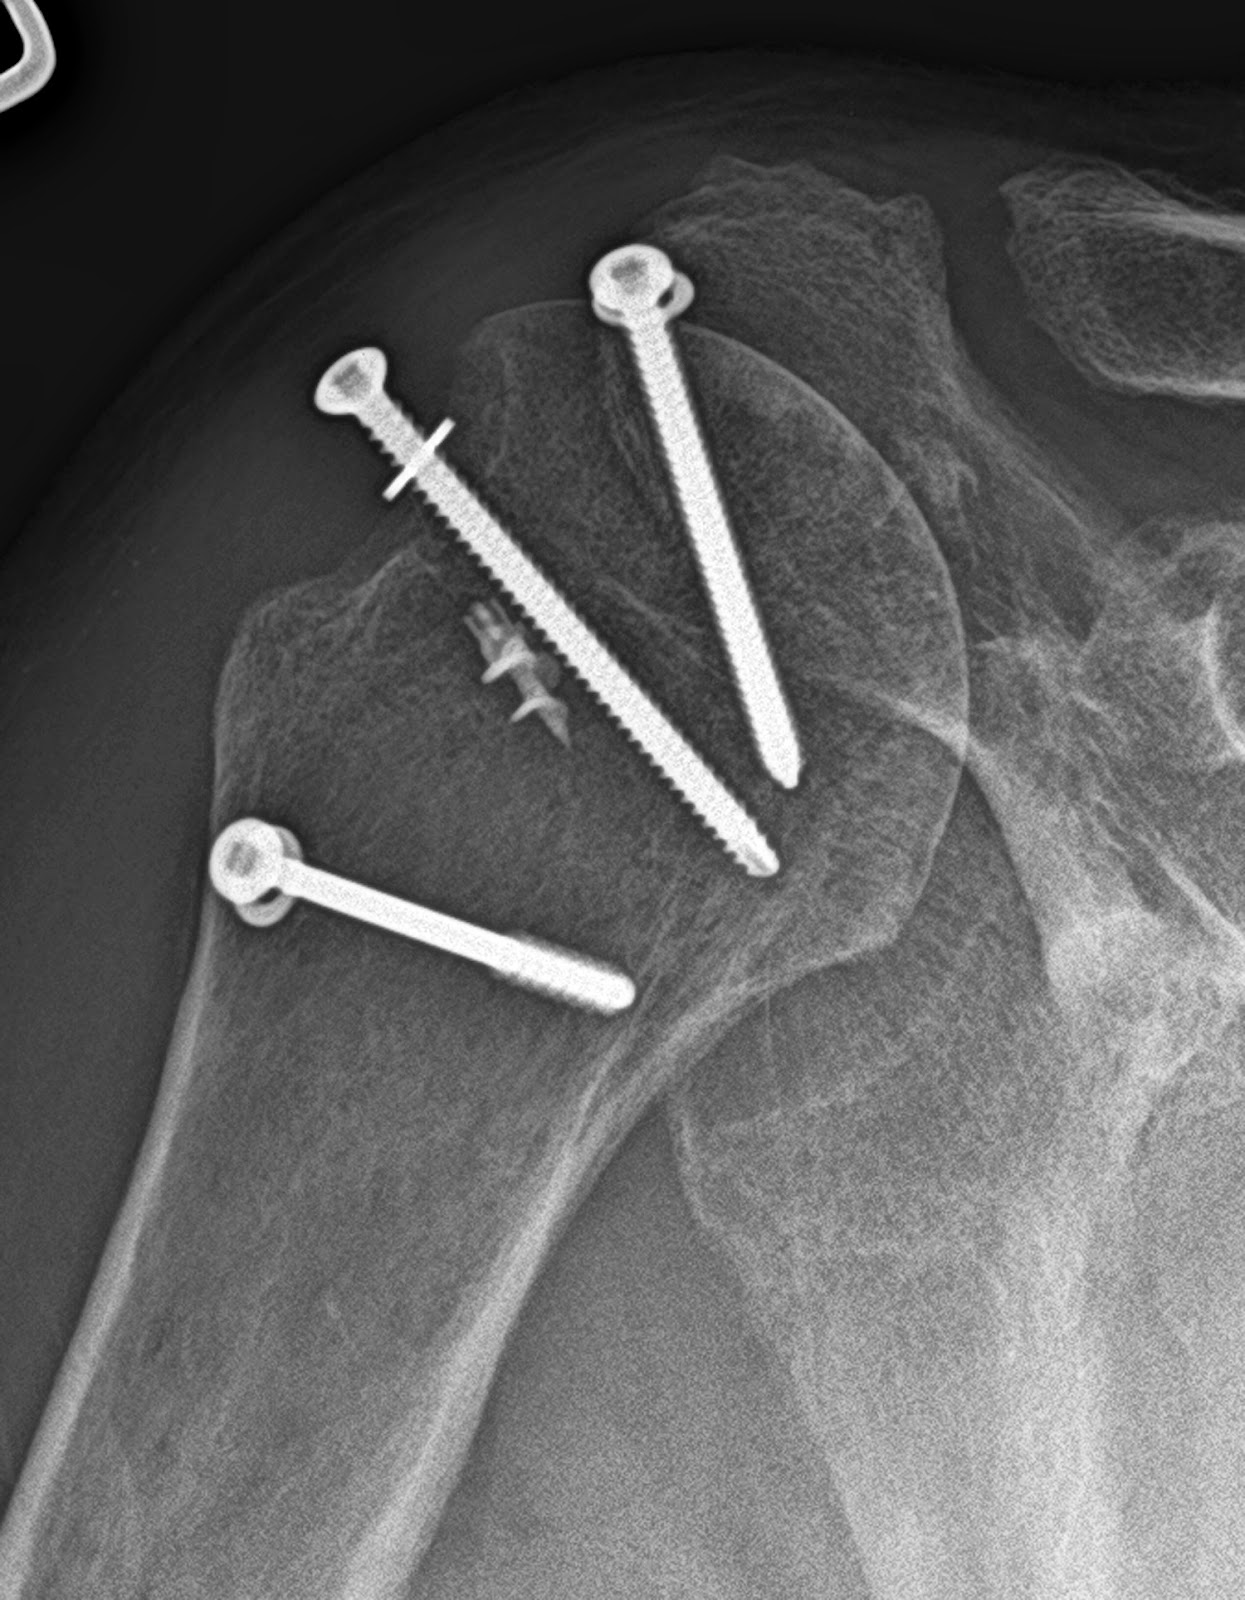

From hyderabadshoulderclinic.com

How Is A Torn Rotator Cuff Repaired? shoulder clinic Hyderabad Rotator Cuff Shoulder Joint Replacement The surgeon removes the top of the arm bone and inserts a metal stem with a. A shoulder replacement is a procedure that tries to eliminate the source of pain and dysfunction by replacing damaged parts of the shoulder joint with artificial components called. The most common reason to consider a reverse prosthesis is when there is arthritis of the. Rotator Cuff Shoulder Joint Replacement.